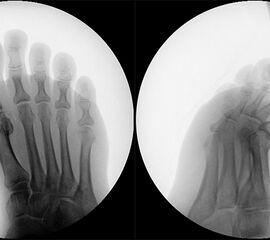

• Röntgen: Fuß belastet in 3 Ebenen.

• Optional MRT und CT bei radiologisch unklaren Verhältnissen.